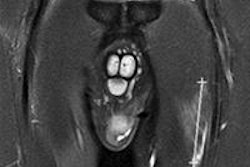

The new version of Quasar MRID3D offers faster isocenter detection, improved fiducial markers, alignment crosshairs, and additional visualization tools, according to the company. The phantom's hollow twin-cylinder wall enclosure now contains 1,502 fiducial markers, with six larger central reference fiducials for use when signal-to-noise ratios are low or when distortion is high.

Quasar MRID3D uses a 3D DICOM viewer with a region-of-interest selector, which gives users the ability to update charts and graphs in real-time to gain further insights into quality assurance. In addition, the phantom's analysis software enables users to perform calculations and execute algorithms to calculate phantom boundary distortion vector field, volumetric 3D distortion vector field, and B0 distortion versus gradient distortion.